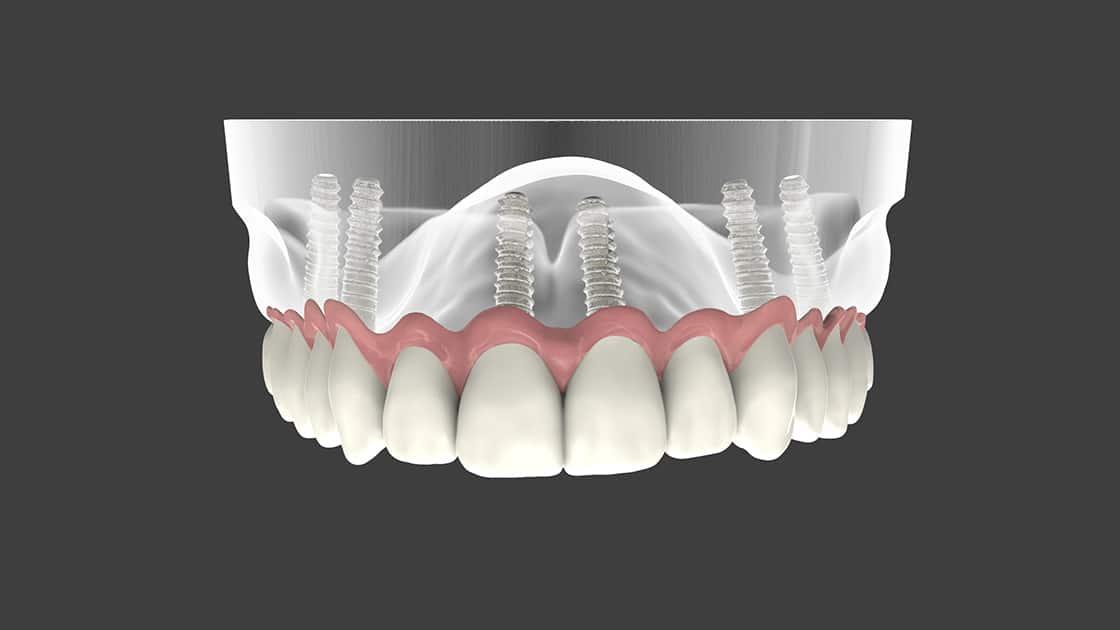

Full Arch Implant Solution

For patients who are missing all of their upper or lower teeth, this unique implant solution replaces a full arch of teeth using only four to six implants.